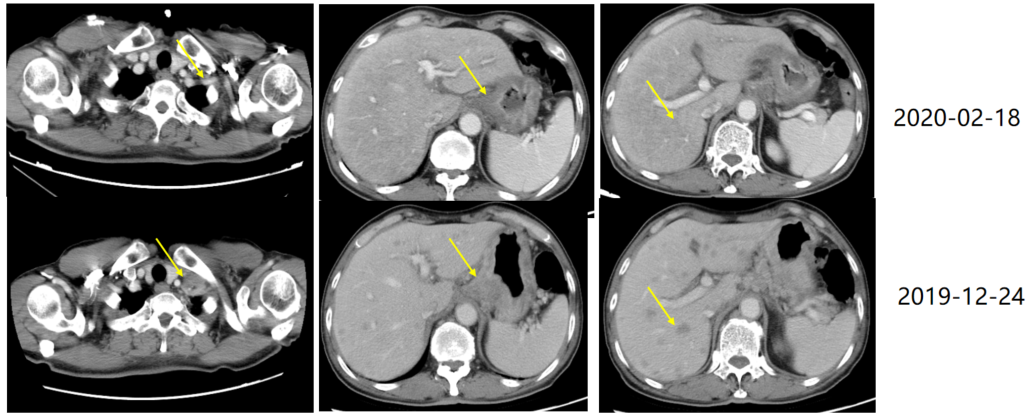

随着临床证据的累积,针对HER2阴性患者,化疗联合免疫治疗已成为一线治疗的标准方案;针对HER2阳性患者,可选择靶向治疗联合化疗+免疫治疗。比如本人经治的一例HER2阳性、PD-L1 CPS=1的晚期胃癌(T3N3M1,IV期,伴肝及多处淋巴结转移)患者,自2020年1月起接受替雷利珠单抗+曲妥珠单抗+化疗一线治疗,2周期后即达部分缓解(PR),6周期后逐步减量进入维持阶段——替雷利珠单抗联合曲妥珠单抗治疗26周期,曲妥珠单抗单药维持16周期。2021年11月评效达完全缓解(CR),直至2025年3月最近一次复查,仍处于CR状态。整体疗程耐受良好,提示替雷利珠单抗联合曲妥珠单抗及化疗方案在HER2阳性、PD-L1 CPS≥1的晚期胃癌中可实现持久缓解与长期生存。